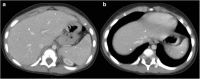

Objectives: We aim to illustrate the multimodal imaging spectrum of hepatic involvement in tuberculosis (TB). Whilst disseminated tuberculosis on imaging typically manifests as multiple small nodular lesions scattered in the liver parenchyma, isolated hepatic tuberculosis remains a rare and intriguing entity.

Methods: Indubitably, imaging is the mainstay for detection of tubercular hepatic lesions which display a broad spectrum of imaging manifestations on different modalities. While sonography and computed tomography (CT) findings have been described in some detail, there is a paucity of literature on magnetic resonance imaging (MRI) features. Due to a significant overlap with other commoner and similar appearing hepatic lesions, hepatic tuberculosis is often either misdiagnosed or labelled as indeterminate lesions. This article is a compendium of cases highlighting the spectrum of imaging patterns that can be encountered in patients with isolated primary hepatic tuberculosis as well as disseminated (secondary) disease. Rare patterns of primary disease such as tubercular cholangitis, hypervascular liver masses, and those with vascular complications are also illustrated and discussed.

Conclusions: Imaging plays a valuable role in the detection of tubercular hepatic lesions. Also, imaging can be helpful in their characterisation and for assessing associated complications.

Teaching points: • Hepatic TB has myriad imaging manifestations and is often confounded with neoplastic lesions. • Imaging patterns include miliary TB, macronodular TB, serohepatic TB and tubercular cholangitis. • Concurrent splenic, nodal or pulmonary involvements are helpful pointers towards the diagnosis. • Miliary calcifications along the bile ducts are characteristic of tubercular cholangitis. • Histological/microbiological confirmation is often necessary to confirm the diagnosis.